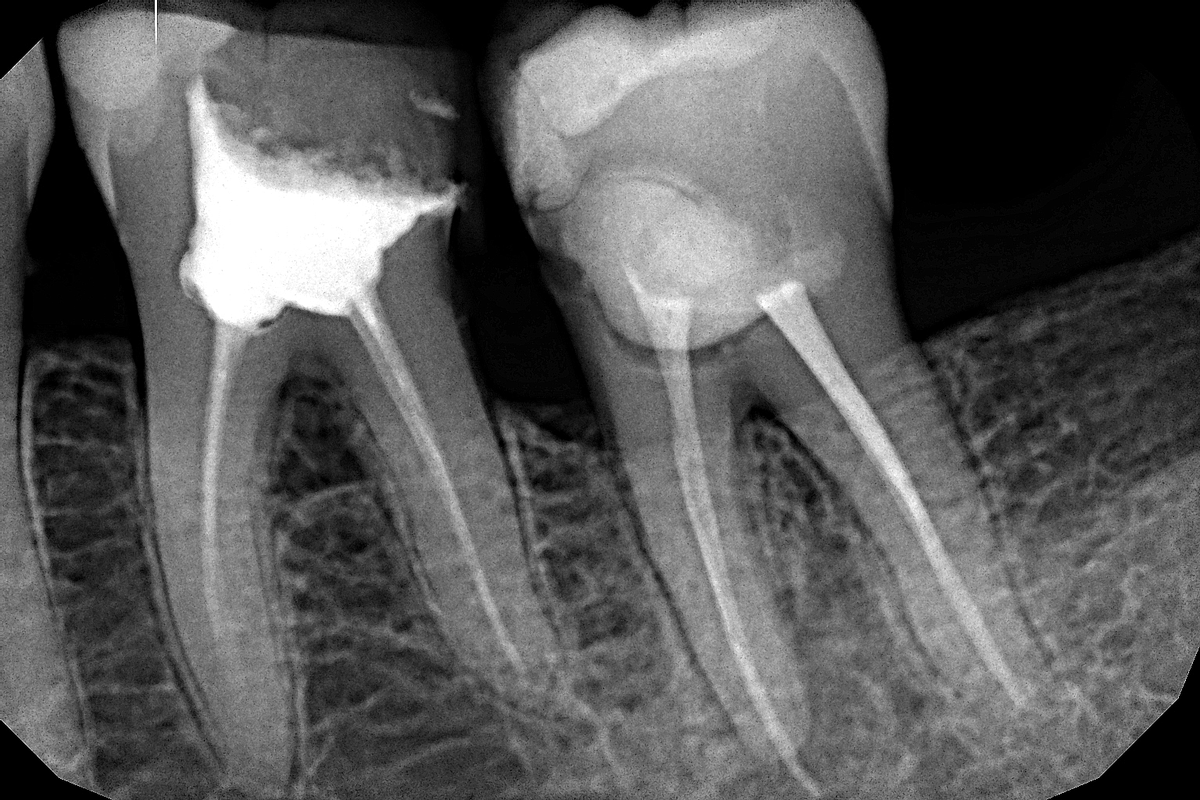

На изображениях твердые ткани и импланты отображаются в светлых тонах. Мягкие ткани слизистой рта видны как серые участки. Если во внутренних структурах образуются кисты, участки нагноение, новообразования с межклеточной жидкостью внутри, то на снимках они выглядят как черные пятна, имеющие четкие неровные контуры.